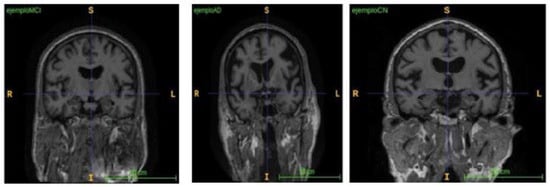

3.1. Multimodal MRI Data Collection

3.2. Image Fusing and Preprocessing